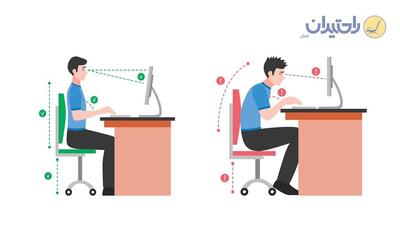

مدیر کل تربیت بدنی سازمان امور دانشجویان اعلام کرد: تقریبا ۵۰ درصد دانشجویان حداقل به یک اختلال اسکلتی عضلانی دچار هستند.

تقریباً 50 درصد از دانشجویان ایرانی حداقل به یک اختلال اسکلتی عضلانی دچار هستند. این آمار مربوط به دانشجویان جدید الورود است و نشان میدهد که کنکور ممکن است تغییرات قابل توجهی در سلامت و تندرستی دانشجویان ایجاد کند.